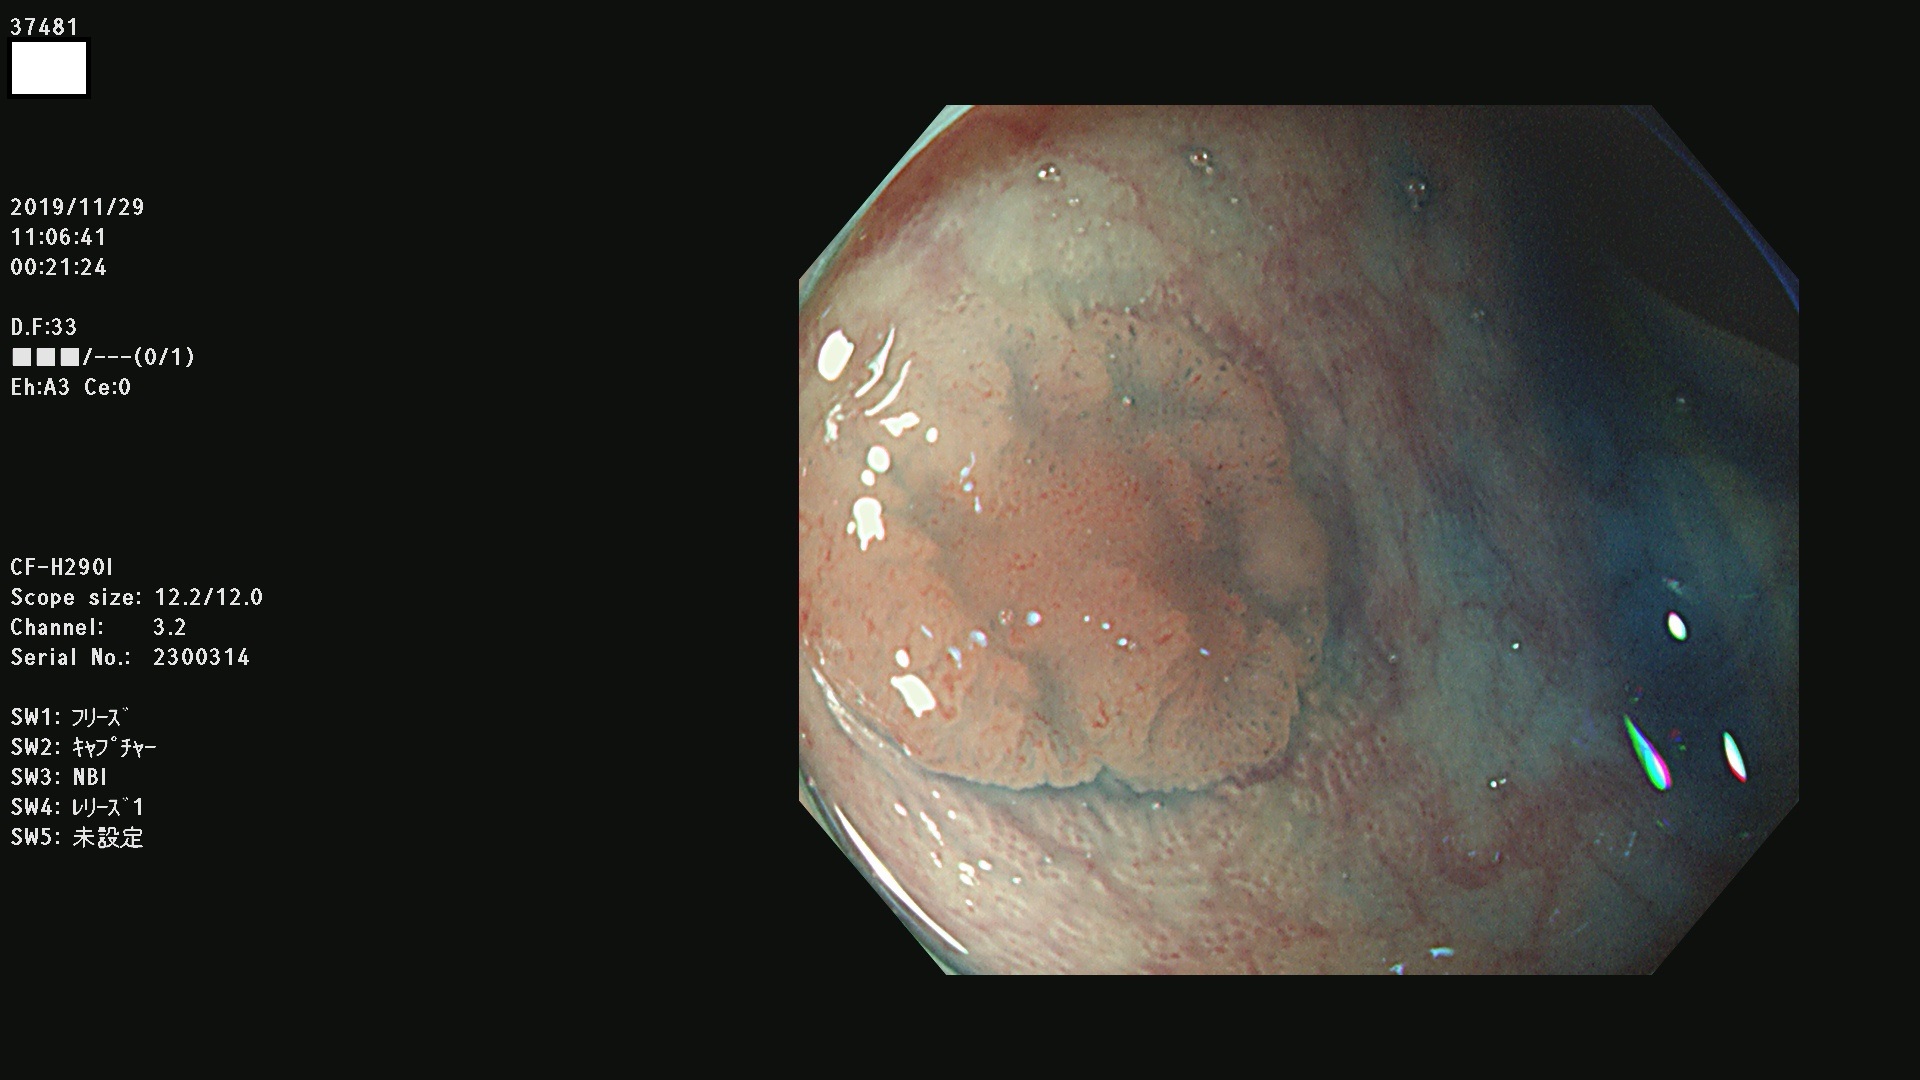

37400(SSAPのみ) 37401 37403 37404 37405 37406 37407 37408 37410 37411 37412 37413 37415 37416 37417 37420 37423 37424 37425 37426 37428 37430(SSAPのみ) 37432 37433 37434 37435 37436 37437 37438 37439 37440 37442 37443 37444 37447 37448 37449 37450 37451 37452 37455 37456 37457 37458 37459 37460 37461 37462 37464 37467 37468 37469 37470(SSAPのみ) 37471 37472 37474 37476(SSAPのみ) 37477 37478 37480 37481 37482 37483 37485 37486 37487 37488 37489 37490 37491 37492 37493 37494 37497 37499

発見困難で危険性の高い平坦型病変(上記100名より抽出)